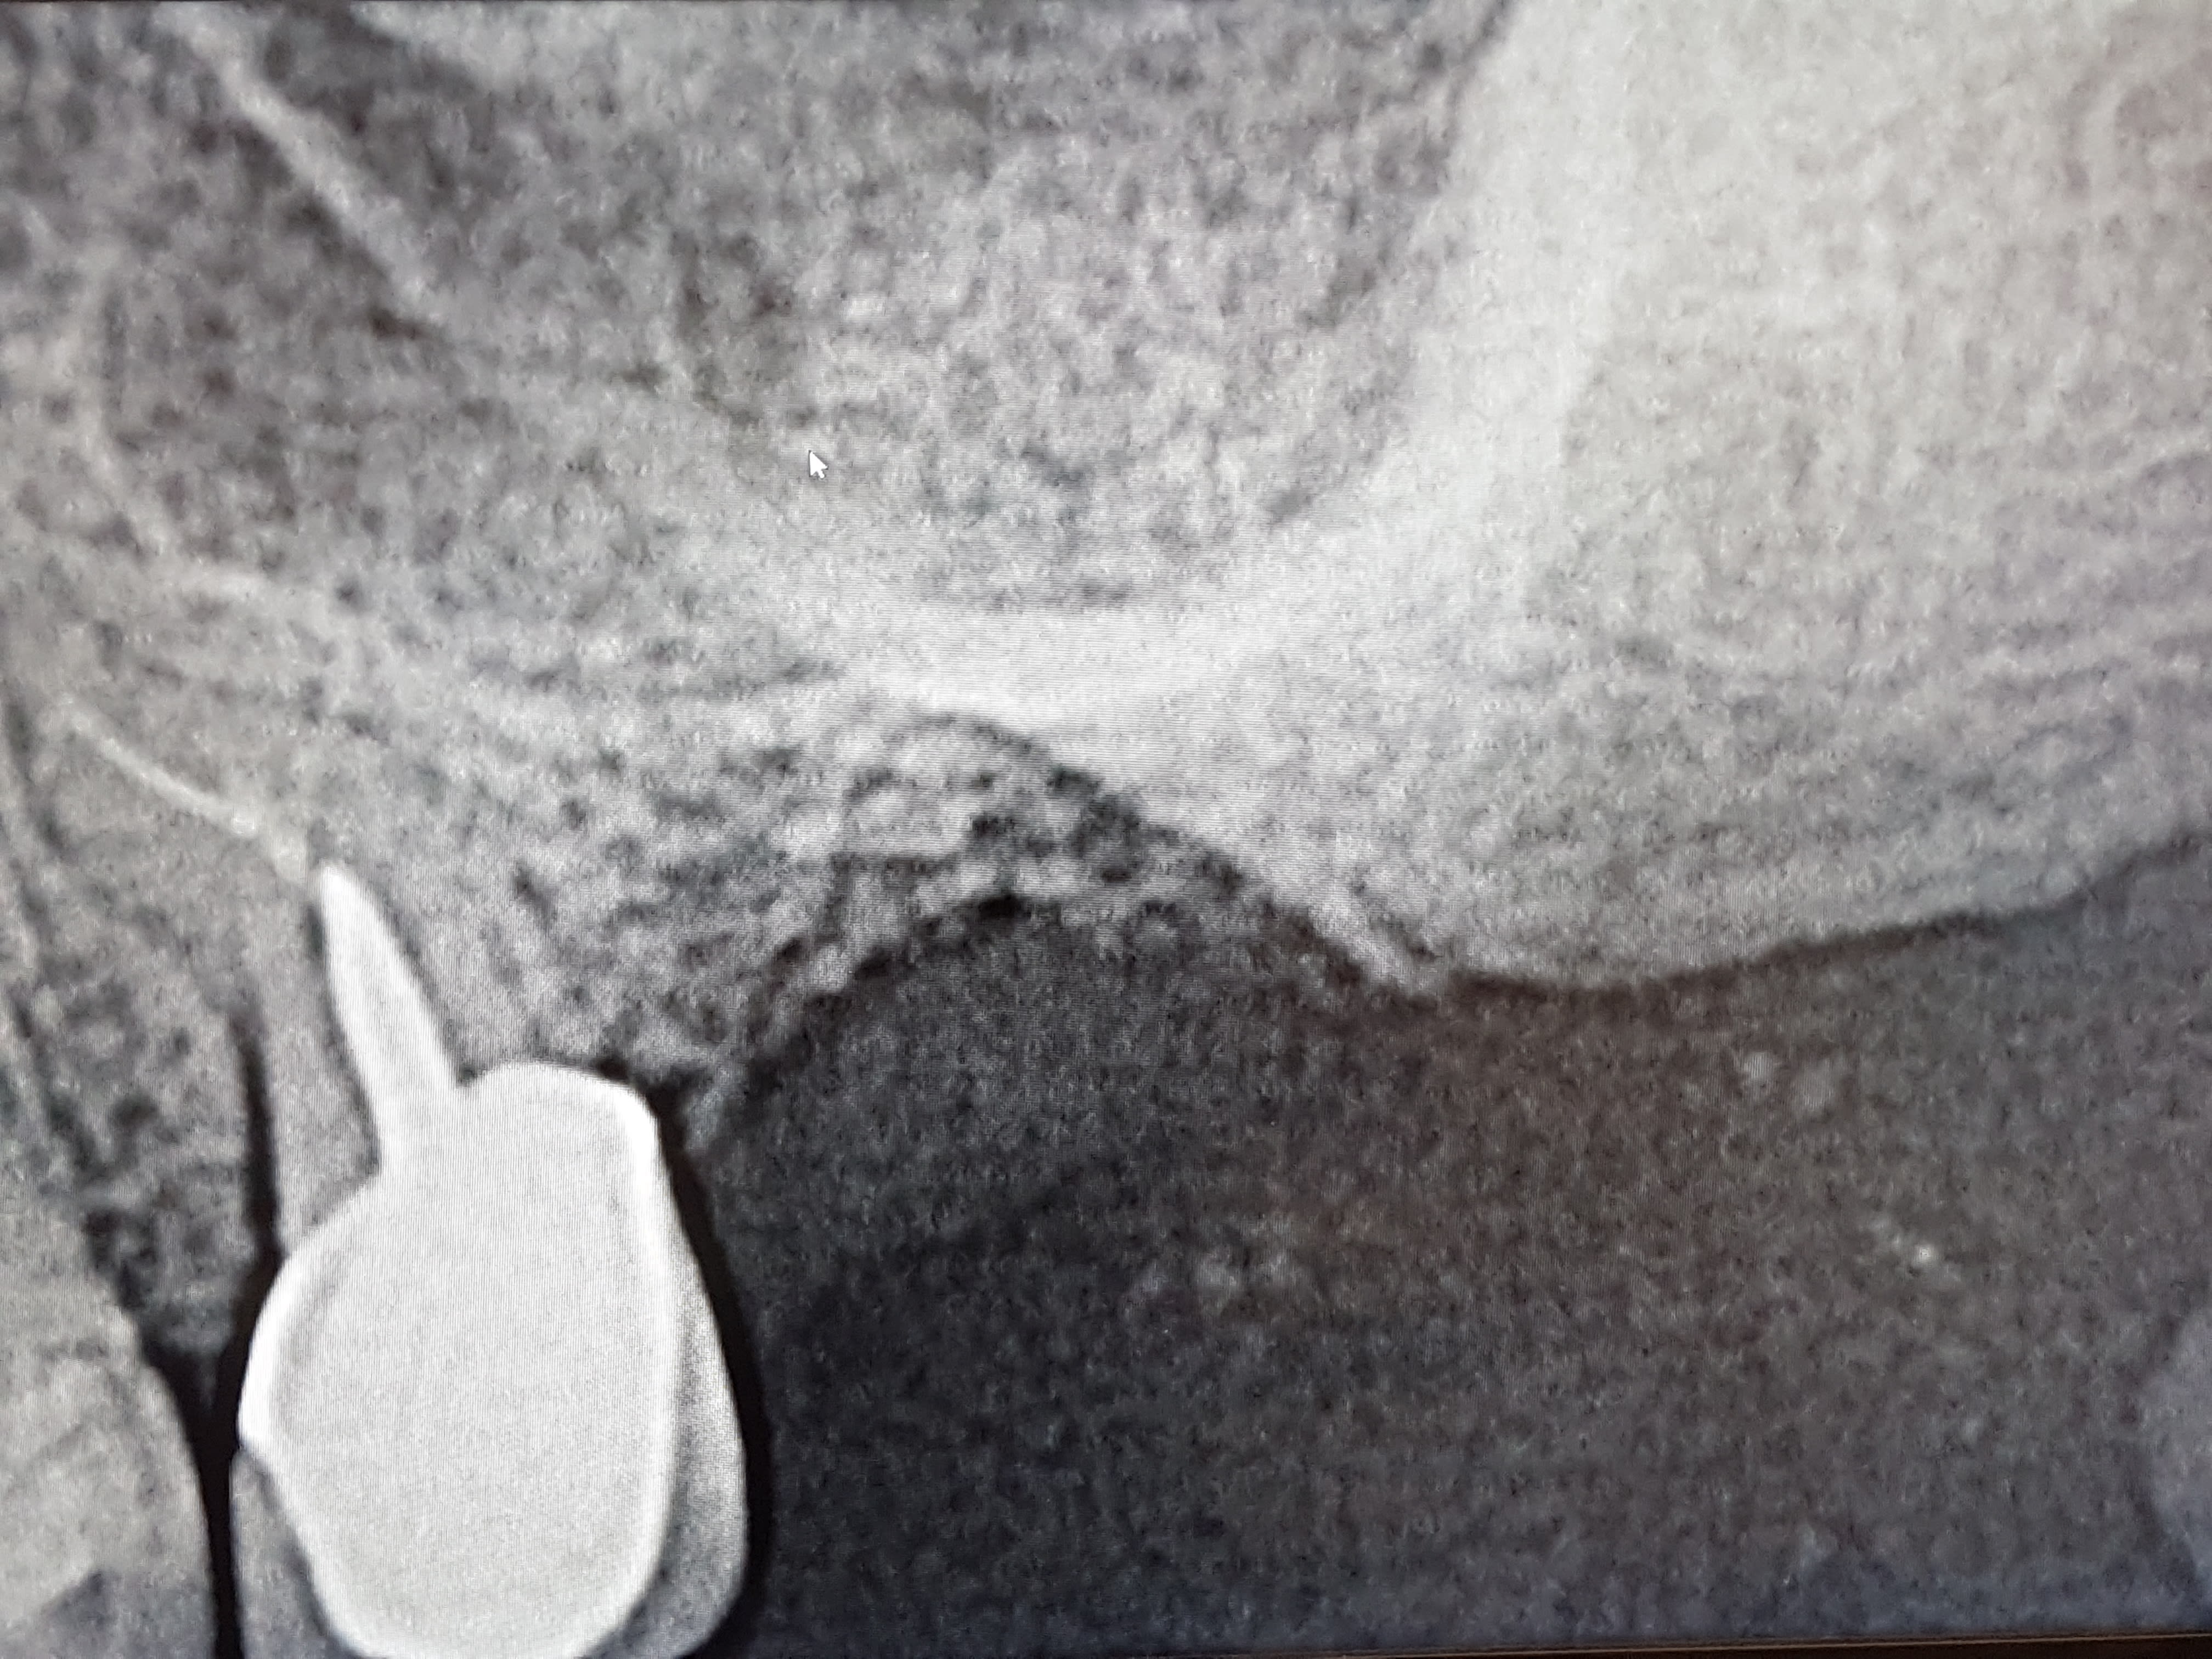

Un autre exemple de l'utilisation des versah. Cas d'EII sur 26, Forage dans le septum et osseodensification. Souleve' de sinus de 5mm mais sans comblement. Controle à 7 jours, aucune douleur post op.

20171018 094131 hjcxwj - Eugenol

20171018 094139 iocwui - Eugenol

20171018 095402 zrdzxf - Eugenol